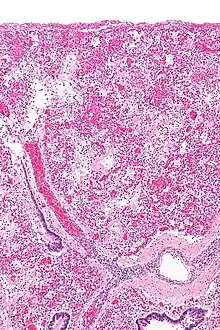

ARDS is a form of fluid accumulation in the lungs not explained by heart failure (noncardiogenic pulmonary edema). It is typically provoked by an acute injury to the lungs that results in flooding of the lungs' microscopic air sacs responsible for the exchange of gases such as oxygen and carbon dioxide with capillaries in the lungs.[12] Additional common findings in ARDS include partial collapse of the lungs (atelectasis) and low levels of oxygen in the blood (hypoxemia). The clinical syndrome is associated with pathological findings including pneumonia, eosinophilic pneumonia, cryptogenic organizing pneumonia, acute fibrinous organizing pneumonia, and diffuse alveolar damage (DAD). Of these, the pathology most commonly associated with ARDS is DAD, which is characterized by a diffuse inflammation of lung tissue. The triggering insult to the tissue usually results in an initial release of chemical signals and other inflammatory mediators secreted by local epithelial and endothelial cells.

Neutrophils and some T-lymphocytes quickly migrate into the inflamed lung tissue and contribute in the amplification of the phenomenon. Typical histological presentation involves diffuse alveolar damage and hyaline membrane formation in alveolar walls. Although the triggering mechanisms are not completely understood, recent research has examined the role of inflammation and mechanical stress.